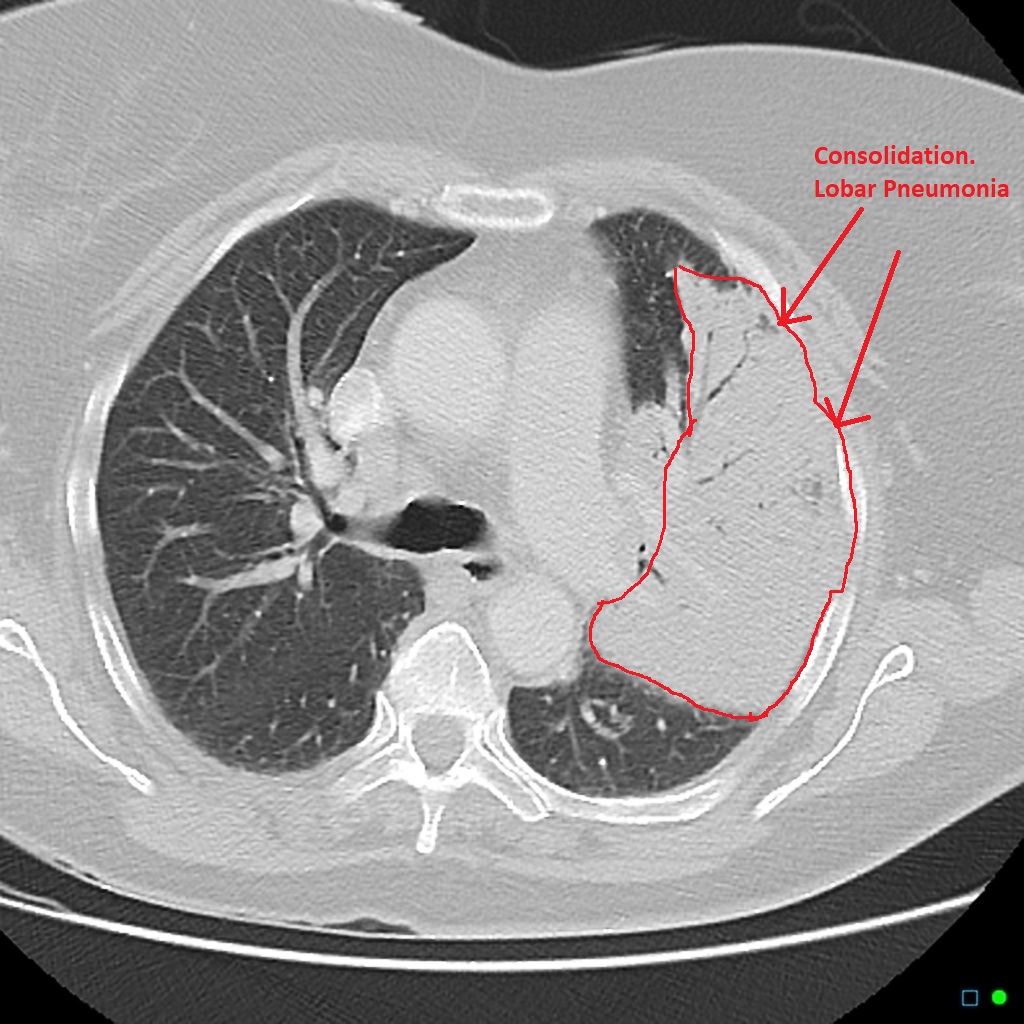

什么是CAP?首先 , 让我们明确CAP的定义 。 CAP是指在医院外罹患的肺实质炎症 , 包括明确潜伏期内入院后发病的肺炎 , 可能由特定病原体感染引起 。 这意味着 , CAP是一种你不希望得到的呼吸道感染 , 可能会在日常生活中找上你 。 那么 , 到底哪些病原体可能导致CAP呢?让我们继续解开这个谜题 。